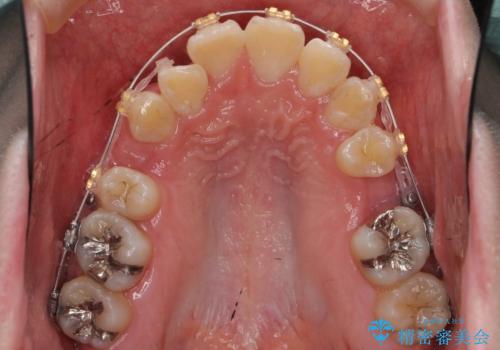

- ワイヤー矯正

- 前歯のがたつき、前突を主訴に来院。

通常前から4番目の歯を抜歯するのですが、左上5番の形が矮小であったため、そちらを抜歯しました。(患者様の希望にそっています。)

前から5番目の歯を抜くと、長くて1年ほど矯正期間が延長しますが、形に異常がない左上4番を抜かずに保存しています。

治療は長くかかりましたが、正常な形の歯をのこすことができました。